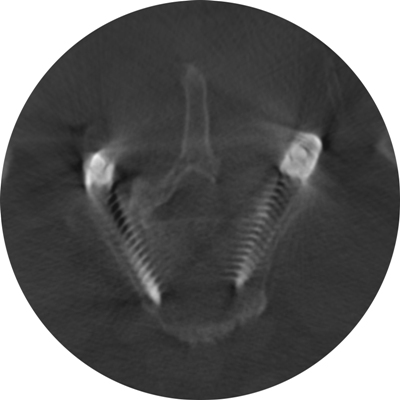

Astfel, în urma unui număr mare de investigaţii suplimentare, a fost luată decizia de a folosi un abord chirurgical numit ”fuziune intervertebrală transforaminală”. Tehnica dată este mai complicată şi mai solicitantă faţă de dotarea tehnică a blocului de operaţii şi a abilităţilor echipei chirurgicale, însă oferă un şir de avantaje pentru pacient.

Deoarece pacientul a fost operat anterior de 2 ori, utilizarea aceluiaşi coridor chirurgical tradiţional putea fi însoţită de un risc mare de leziuni a nervilor şi vaselor în canalul spinal. De aceea, a fost aleasă o cale mai puţin utilizată în practica cotidiană, dar care a fost cea mai raţională pentru pacientul dat, aşa-numitul abord paramedian transmuscular sau abordul prin spaţiul Wiltse.

Este un caz fericit pentru pacientul din Italia şi de succes pentru secţia Neurochirurgie, dar şi pentru întreaga instituţie medicală, or, astfel de intervenţii complicate au devenit posibile în Republica Moldova în urma deschiderii noului Bloc chirurgical în luna mai curent, prin intermediul căruia ţara noastră a obţinut facilităţi şi posibilităţi care au existat pînă nu demult doar în centrele medicale contemporane performante din lume. Astfel, sala de operaţii Hybrid a blocului dispune de metode de neuroimagistică intraoperatorie şi sisteme de monitoring şi neuronavigaţie, sisteme specializate de implanturi din titan şi instrumente chirurgicale, echipamente pentru disecţie osoasă. Acest complex chirurgical este completat de un departament ultradotat de anestezie şi neuroreanimare, care asigură o parcurgere perioperatorie fără complicaţii.